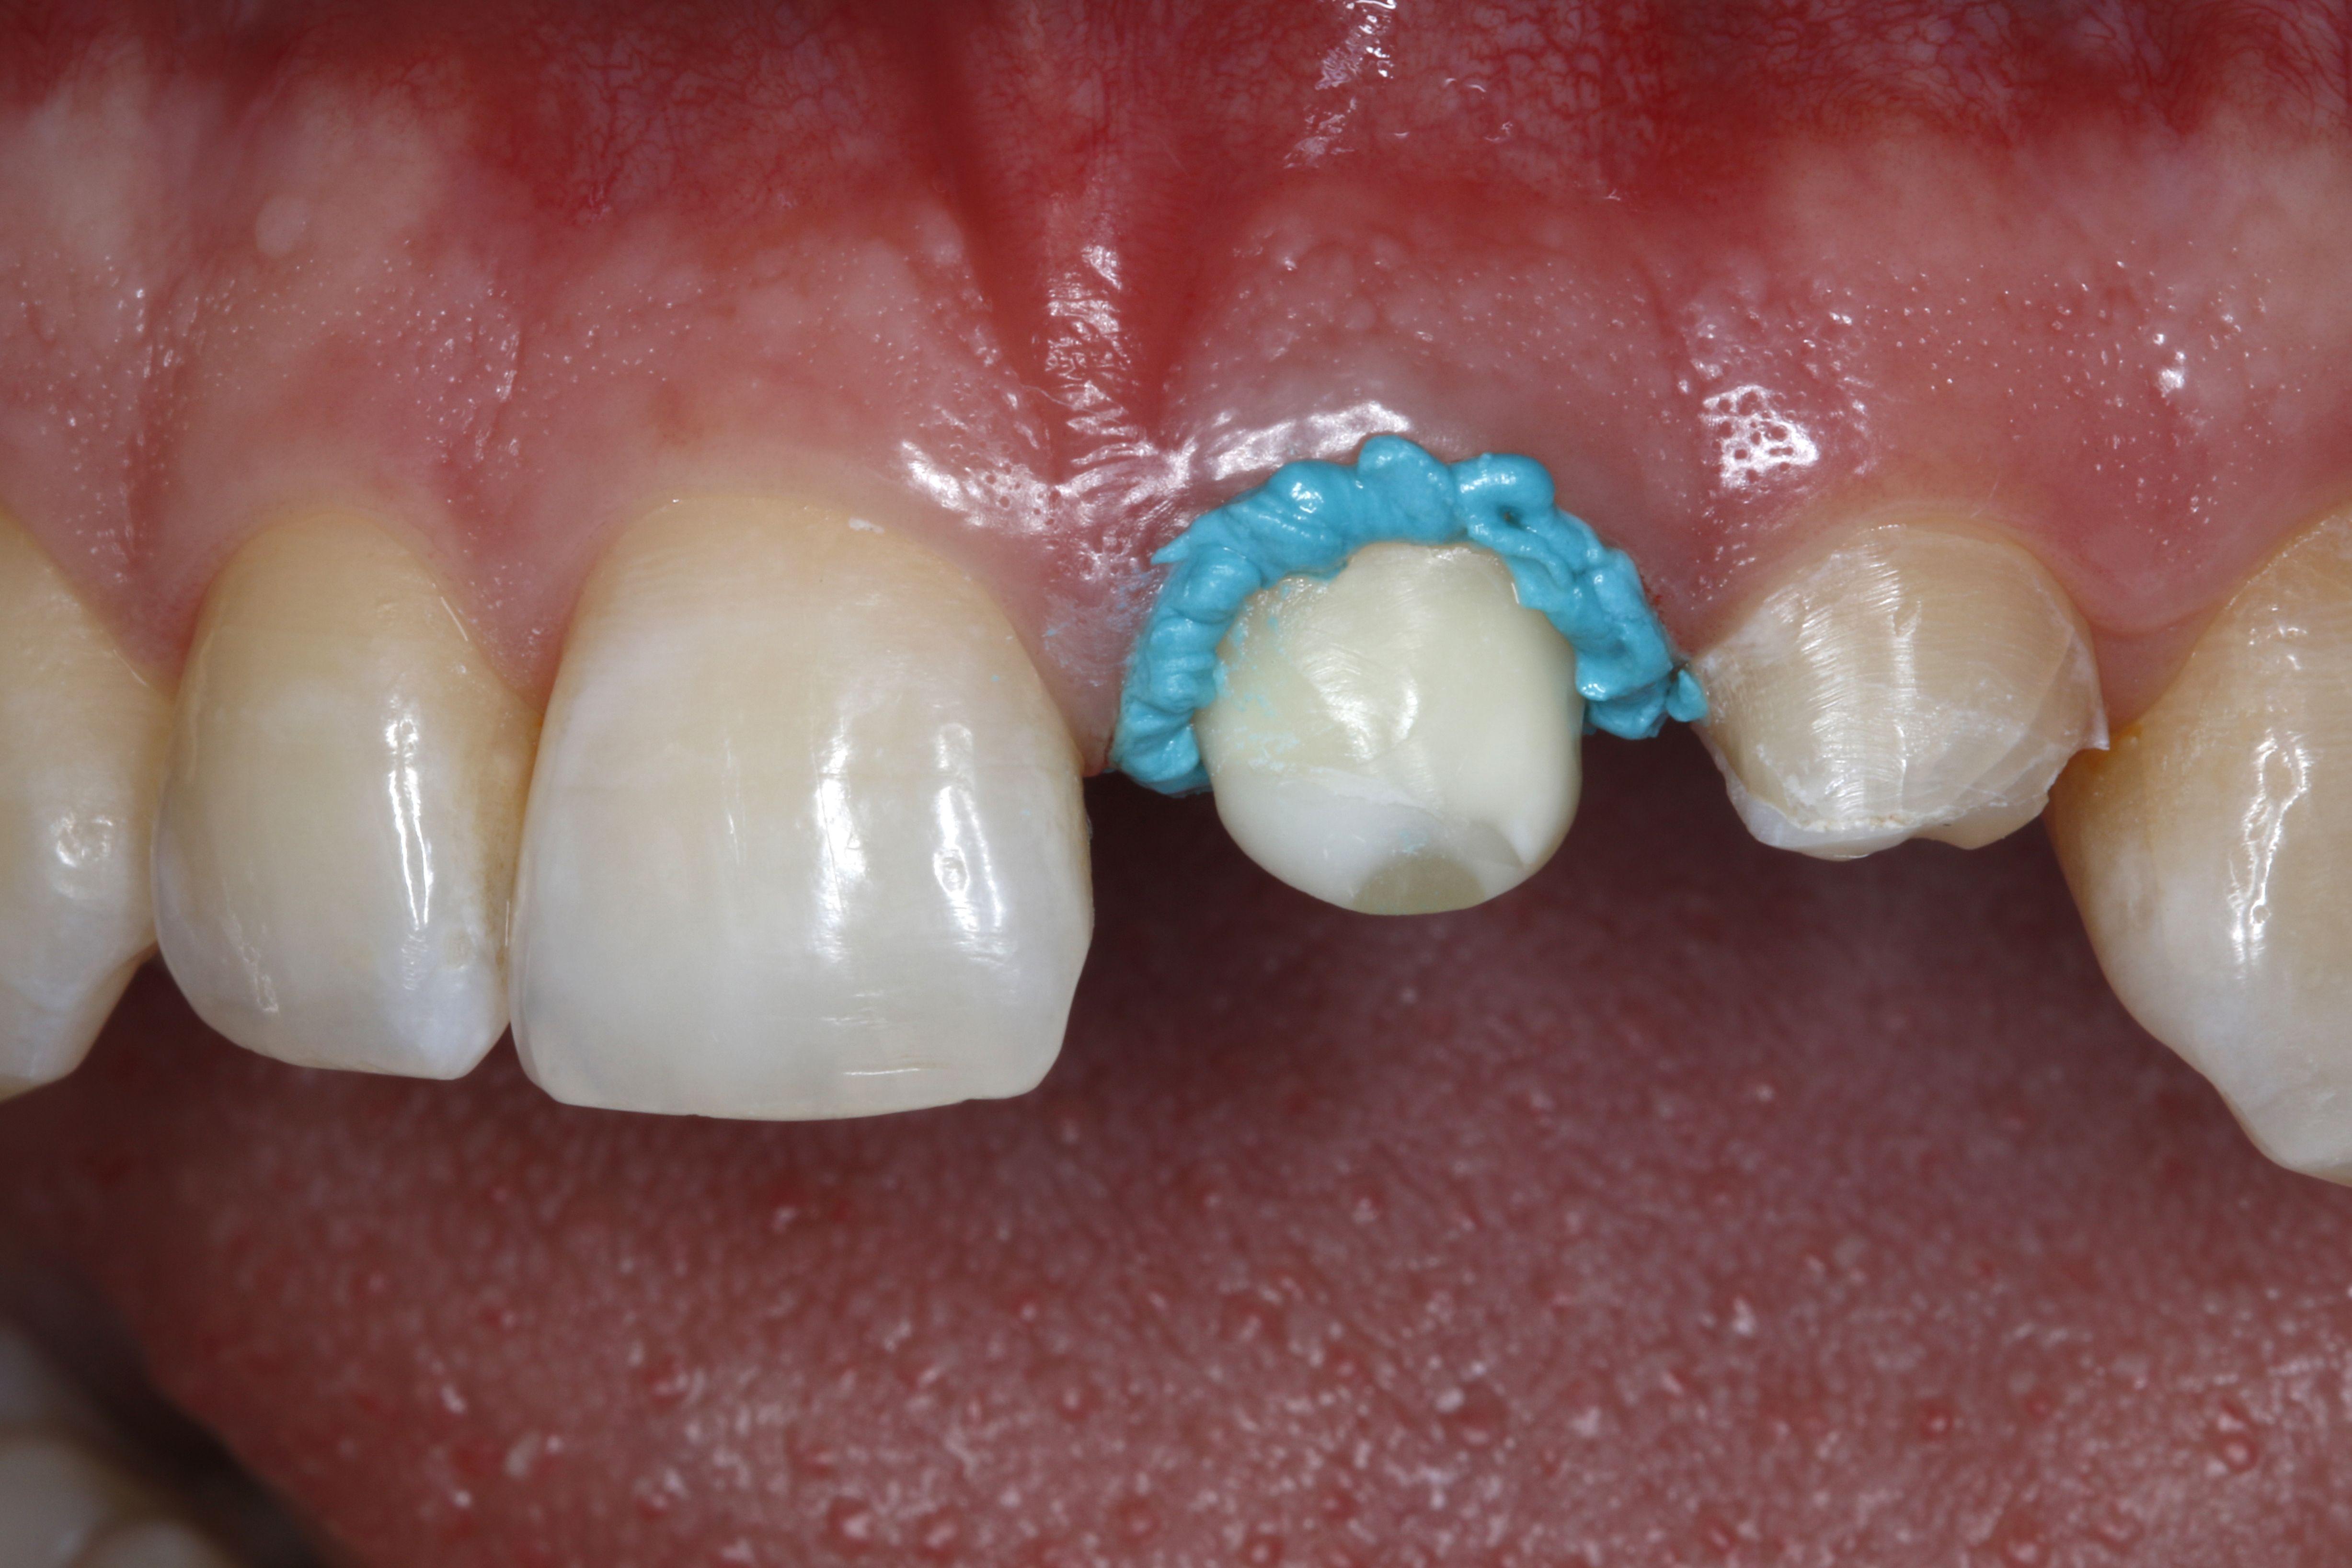

Ryc. 7. Ząb 21 od strony brzegu siecznego – zwraca uwagę stabilna konsystencja pasty retrakcyjnej, która utrzymuje się na miejscu po aplikacji i nie spływa.